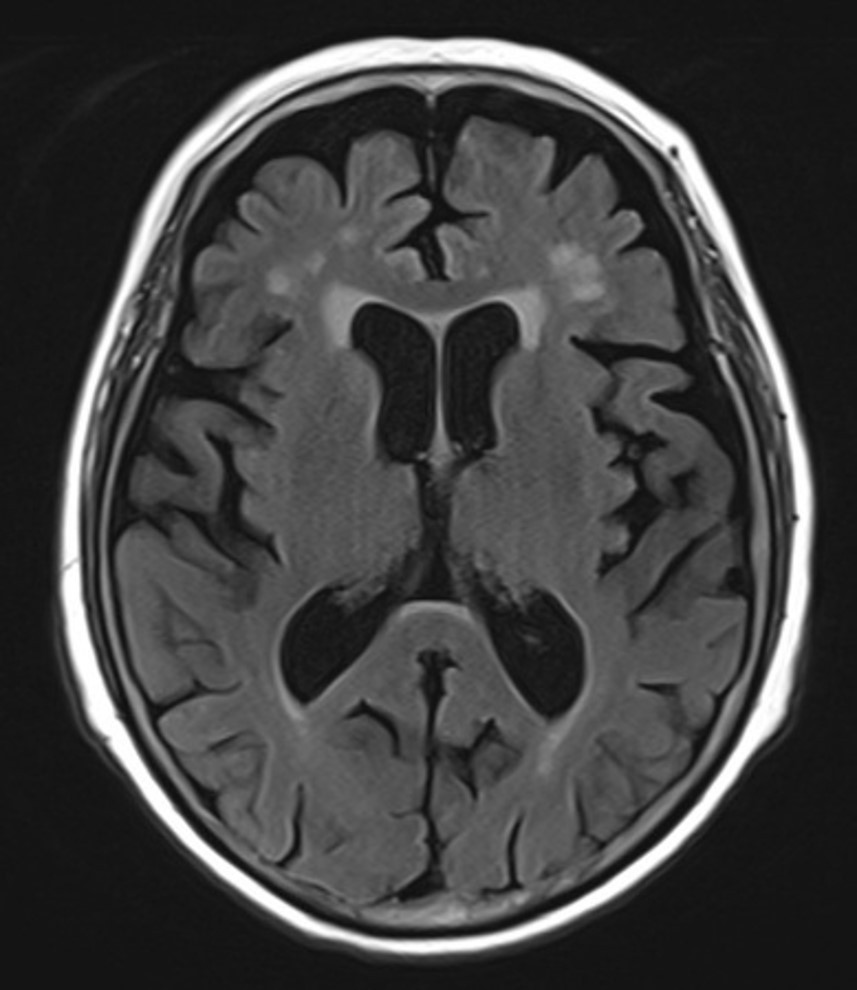

뇌 MRI에서는 급성 뇌경색 같은 건 없었지만

연령에 비해 뇌위축이 진행되어 있었어요.

그림4.jpg 촬영 일시: 2025.05.02

<Fig 1. 뇌 MRI>

그리고 MMSE 점수가 22점...